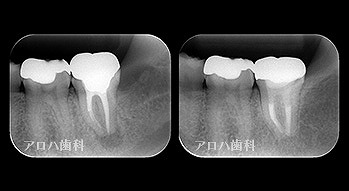

透過像が消失したケース

case1

初回根管治療

1年予後

治療回数1回

case2

左の透過像の変化(5年予後)

(のちに右も壊死により根管治療)